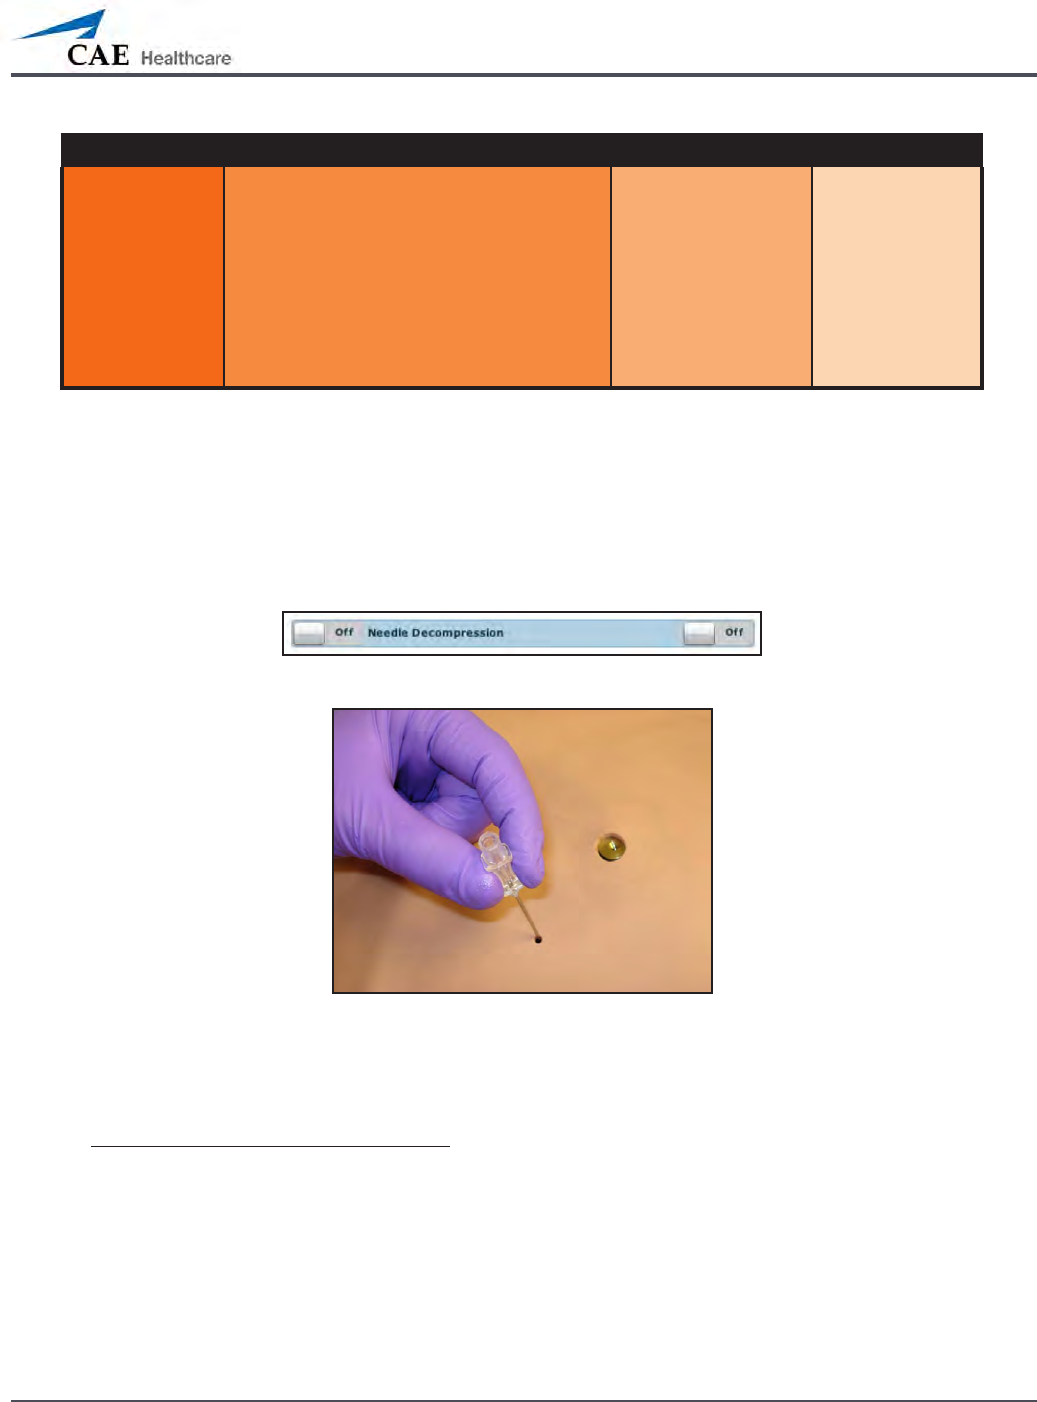

Needle Decompression (Prehospital Only)

Needle decompression can be performed bilaterally into a small hole located in the

midclavicular line of the second intercostal space using a 14-gauge needle.

To enable the Needle Decompression feature, activate the switch for the appropriate side(s).

From the Respiratory view, turn the desired Needle Decompression switch to On.

Needle Decompression Switch

Needle Decompression

When a needle is inserted in the second intercostal space, along the midclavicular line, air is

released while intrapleural volume is present.

Needle Decompression and Chest Tube

When using the METIman Prehospital system, the Needle Decompression and Chest Tube

features can be enabled simultaneously. Intrapleural volume will decrease when both are in

use.